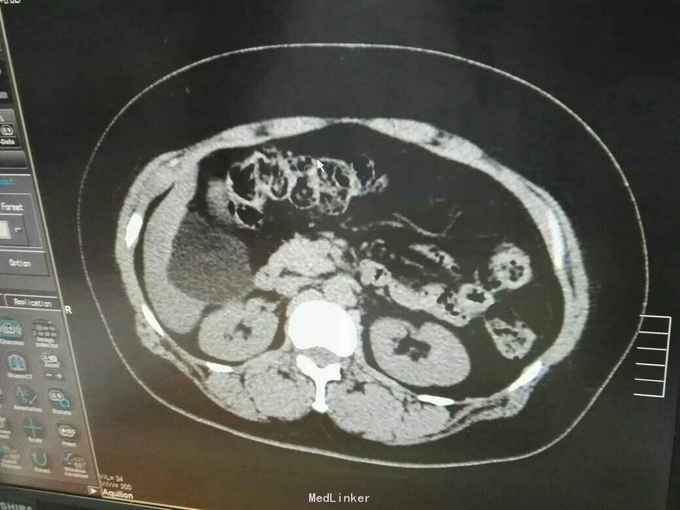

巨大肝囊肿

发现肝脏占位10年

肋弓下可触及囊性占位

肝囊肿

今日在局麻下行囊肿穿刺抽吸+无水酒精注射术 术中共抽取淡黄色液250ml